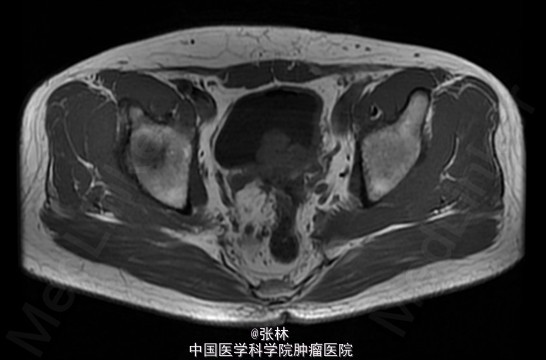

CT:膀胱充盈尚可,内见积气、气液平面;膀胱后壁明显不规则增厚,形成肿物,边界不清,范围约4.8×2.8cm,膀胱壁外缘毛糙,局部与直肠前壁分界不清。考虑:膀胱后壁肿物,与直肠关系密切,考虑为恶性。 MR:膀胱左后壁肿物,与精囊腺及后方直肠分界不清,膀胱充盈状态不同,形态较前改变,现范围约3.6×4.2cm,边界不清楚,T1WI呈低信号,T2/FS呈高信号,DWI扩散受限,增强扫描呈明显不均匀强化,考虑为恶性。